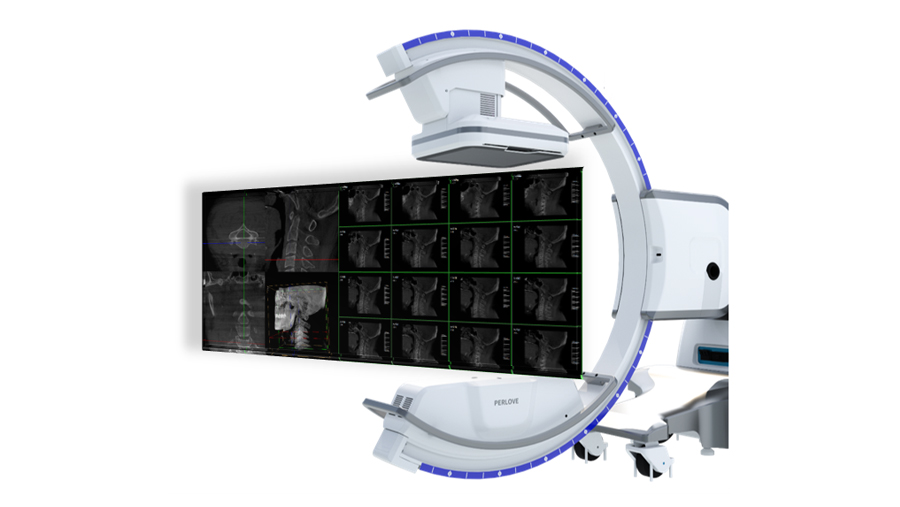

术中三维成像和橫断面图像提供多角度的手术诊断信息,辅助医生进行术中评估判断,诸如骨折复位情况和内植入螺钉的尺寸和位置,辅助手术更好地完成。

提供更大的术中三维成像视野,采集更多图像信息,可一次拍全全段颈椎、全段腰椎、七节胸椎、双侧骶髂关节、股骨头及单侧盆骨。

在C臂扫描过程中,始终保持拍摄主体处于射线束的中心,避免了序列图像采集过程中的横纵方向运动,减少相对运动造成的运动伪影。

平板垂直升降运动 便于术中微调平板与拍摄主体的距离,更加贴近病灶体,成像范围更大,图像更清晰。